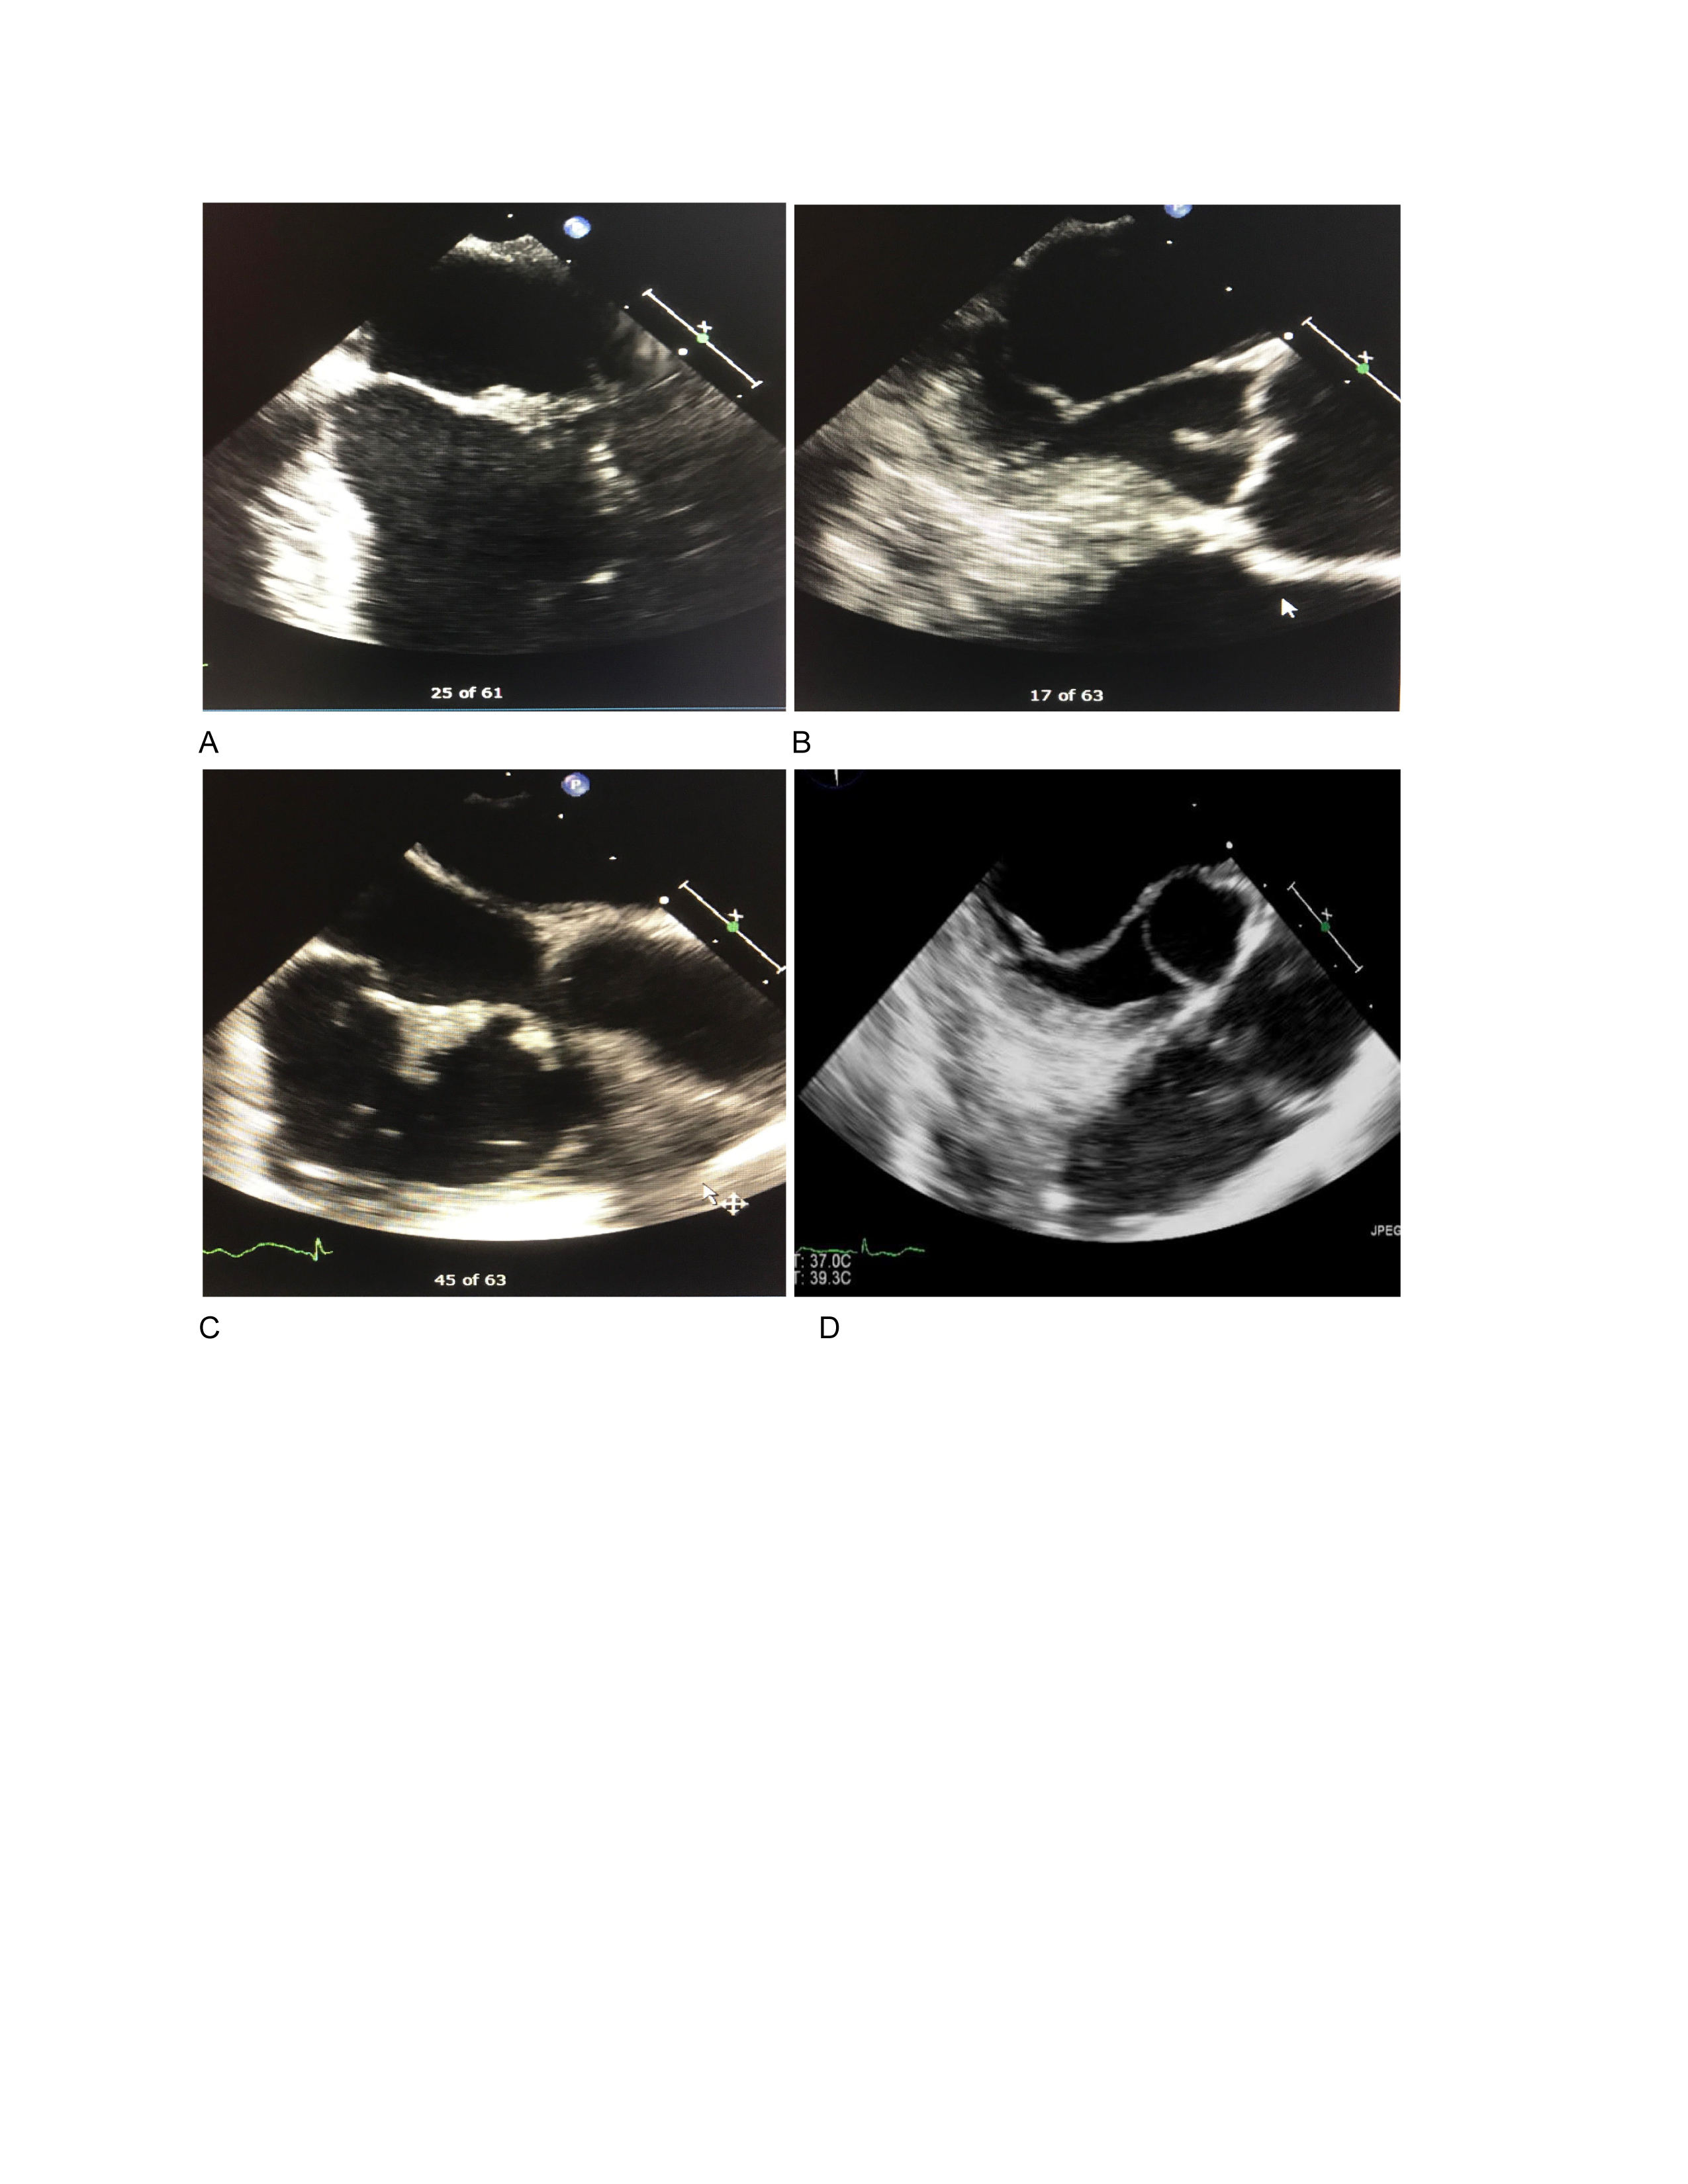

Transthoracic echocardiography (TTE) revealed thickening of aortic, mitral, and tricuspid valves and possible mobile, soft-tissue masses consistent with vegetations on the aortic and mitral valves.

Transesophageal echocardiography (TEE) revealed soft-tissue masses consistent with vegetations on all valves (Aortic valve 12 x 3 mm, Mitral valve 13 x 3 mm, Tricuspid valve 14 x 19 mm and Pulmonic valve: ill-defined mass).

In this case, cardioembolic stroke was suspected and the TTE was performed which revealed possible vegetations leading to the TEE finding of quadruple-valve endocarditis.